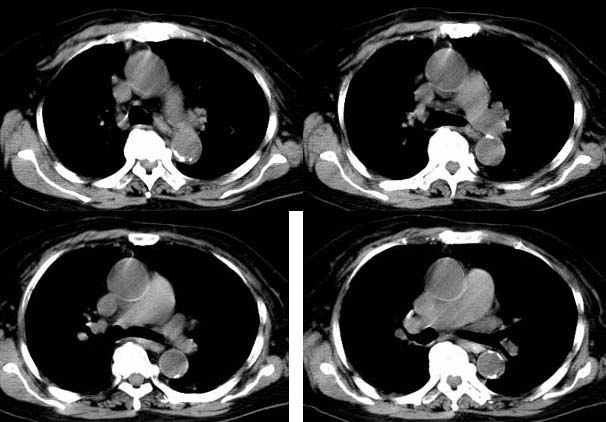

请大家讨论右下肺占位性质。ct值约35-55hu

右肺门后侧软组织肿块,内见点状钙化,年龄76,ct值约35-55hu ,考虑肺癌可能

考虑右肺中心型肺癌并纵隔淋巴结肿大。建议支气管镜鉴。

右下肺,右肺门后方见团块状软组织密度影,边缘呈分叶状,其内见斑点状钙化,肿块内部支气管腔闭塞。肿块后方可见胸膜尾征,外侧方见斑片状模糊阴影。右肺门淋巴结增大。

考虑:右侧中央型肺癌伴阻塞性肺炎及右肺门淋巴结转移

右肺门后侧环绕支气管的软组织肿块,内见点状钙化,远端有阻塞性炎症,年龄76,ct值约35-55hu ,考虑右肺中心型肺癌。建议支气管镜鉴。